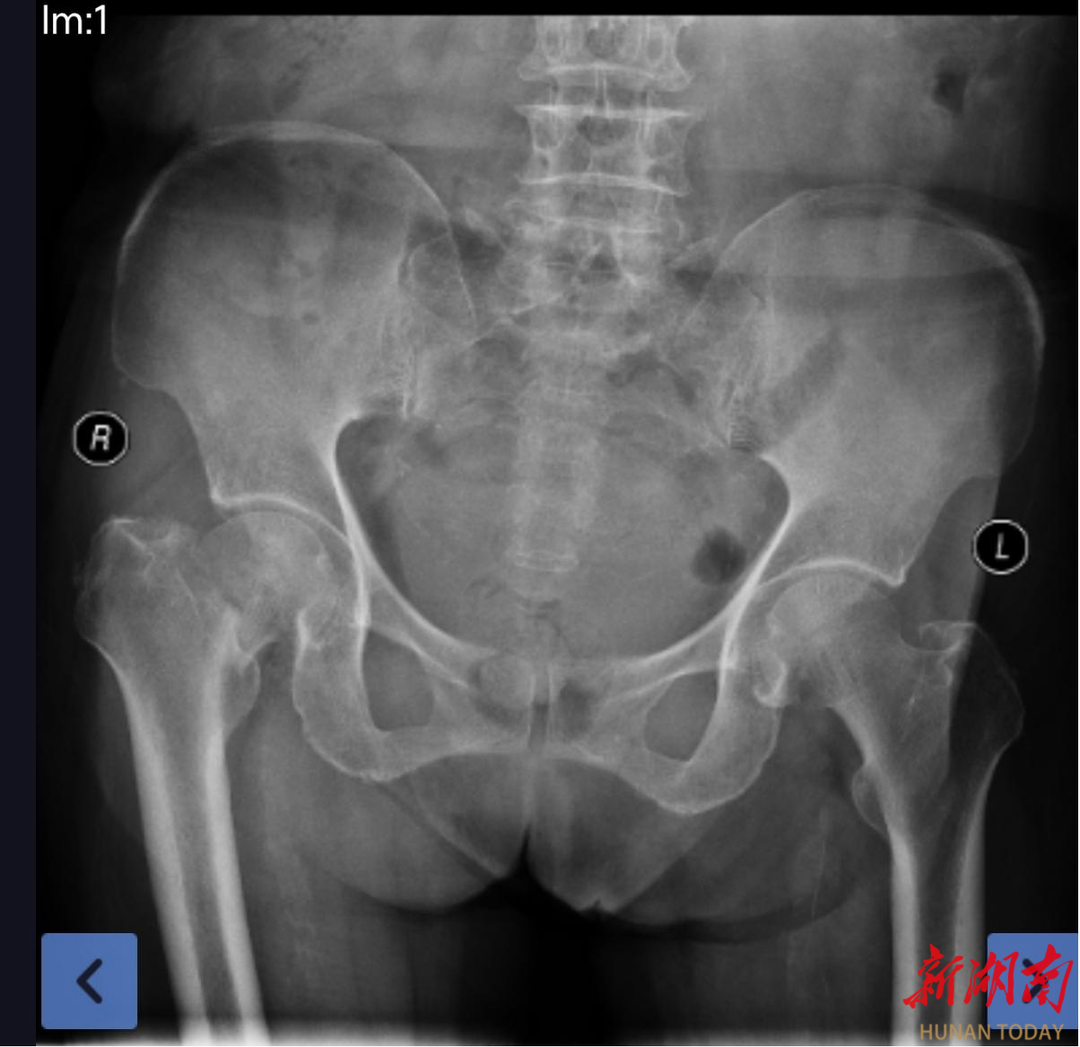

此前,辰溪县103岁徐老在家中不慎跌倒,被送入湖南医药学院总医院关节手外科治疗。经检查诊断,患者右侧股骨颈骨折,自身还伴有高血压3级(极高危)、肺部慢性炎症等多种基础疾病,手术耐受性极差,风险极高。

(术前X片检查)